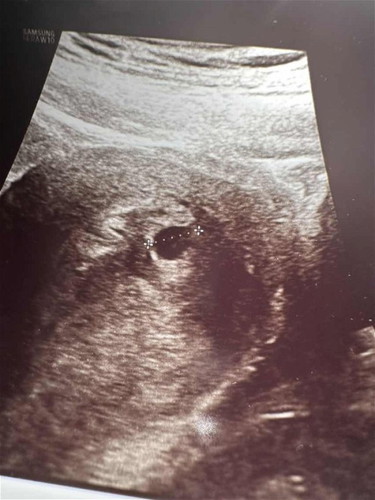

Yolk sac or empty gestational sac?

Hi mummies, is there a tiny yolk sac (upper right) shown on this ultrasound scan? Or does it look just like an empty gestational sac to you?

I think still too small to see! When I did my scan in week 5+, the yolk was very obvious so I think still need to wait a bit more 😅

Definitely looks like theres small yolk sac! As theres something attached inside

Yea i thought so too. But during the scan when i asked the doc if there’s yolk he said no too early 😅 but i thought i really saw something? 🤣